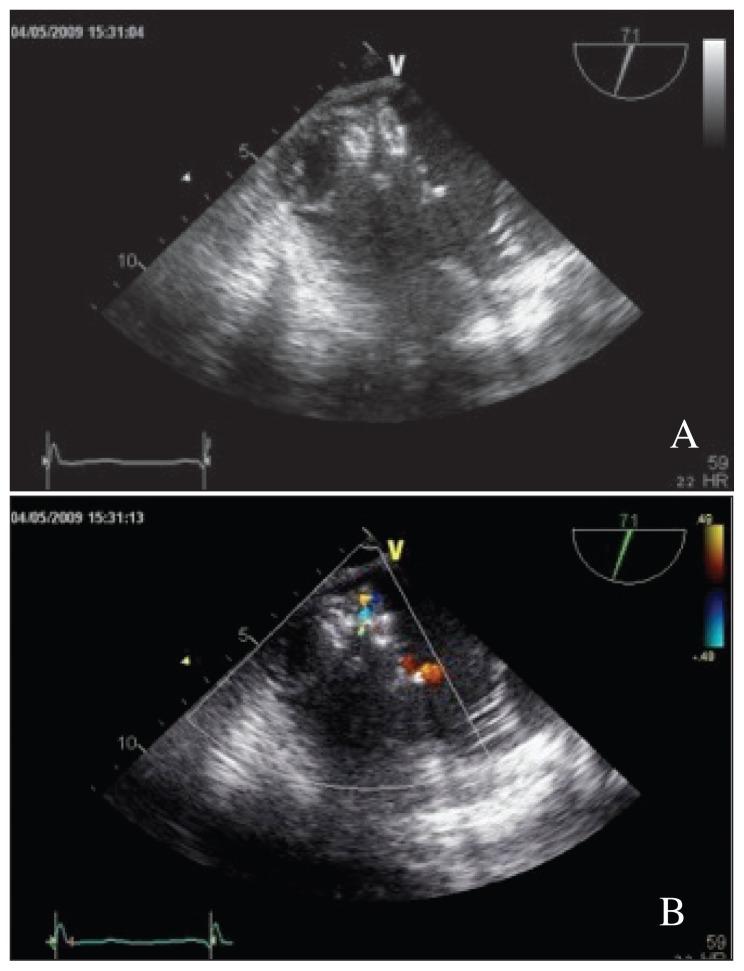

Ventricular septal defect (VSD) is a life-threatening complication of transmural myocardial infarction. Urgent surgical repair and concomitant revascularization are the standard of care. Percutaneous catheter-based closure techniques have been reserved for patients with a high-risk surgery or a failed surgical procedure with residual shunting. This case report demonstrates the successful transcatheter closure of residual VSD using the Amplatzer muscular VSD device (Amplatzer, Minnesota, USA) after surgical patch dehiscence for postinfarction VSD and 3-and-a-half years' post-intervention follow-up.

室间隔缺损(VSD)是透壁性心肌梗死的一种危及生命的并发症。紧急手术修复及同期血运重建是治疗的标准方法。经皮导管封堵技术一直用于手术风险高或手术失败且有残余分流的患者。本病例报告展示了在心肌梗死后室间隔缺损手术补片裂开后,使用Amplatzer肌部室间隔缺损封堵器(美国明尼苏达州的Amplatzer公司)成功经导管封堵残余室间隔缺损,并进行了干预后3年半的随访。